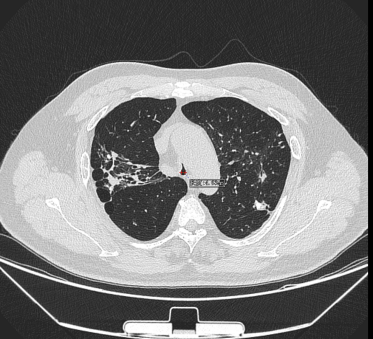

日前,患者趙先生(化名)因進行性呼吸困難來到河南省胸科醫(yī)院尋求治療,經(jīng)檢查確診為支氣管結(jié)核導致氣管中下段重度瘢痕性狹窄,最窄處直徑僅約3mm,且局部軟骨環(huán)破壞、塌陷,這意味著支撐氣道的結(jié)構(gòu)遭到損毀,通氣功能嚴重受損,且因狹窄部位靠近隆突,治療操作風險極高,稍有不慎就可能導致大出血、氣道完全閉塞等致命并發(fā)癥。

在硬質(zhì)支氣管鏡引導下,手術(shù)團隊首先對狹窄部位進行球囊擴張。隨后,將術(shù)前根據(jù)患者三維CT數(shù)據(jù)定制的Y型硅酮支架精準覆蓋于氣管狹窄段。該支架確保與患者自身的氣道解剖結(jié)構(gòu)完美貼合,實現(xiàn)最佳支撐效果,并最大限度減少粘膜刺激增生等特點。支架展開后穩(wěn)定支撐于隆突及雙側(cè)主支氣管,氣道狹窄立即得到解除。